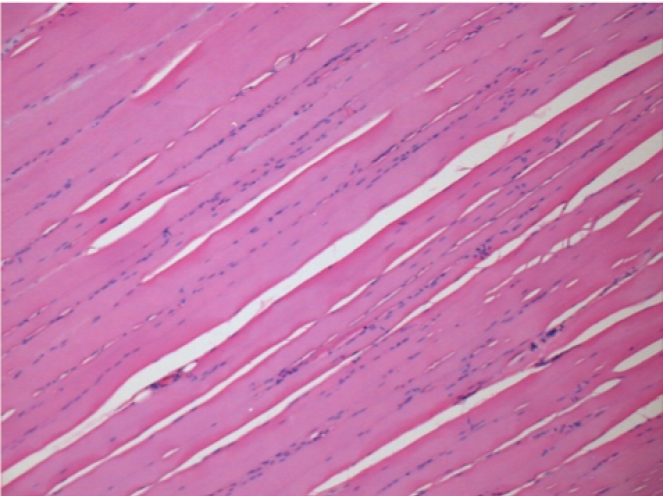

7 ay (D210) Endopeel IM Enjeksiyonundan sonra sağ pretibial kasta 0,1 ml.

7 ay sonra Restitutio reklam entegrasyonunu tamamlayın

Sol : Kontrol 50xD210

Sağ 50X-D210

Endopeel, yaklaşık olarak 1 aylık bir periyotta seçici bir geri dönüşümlü miyofibroliz ve inflamatuar reaksiyonu indükler.

Kas değişiklikleri neredeyse tam olarak geri döndürülebilir

Çalışmanın her yerinde nekroz veya apse bulunmadı.